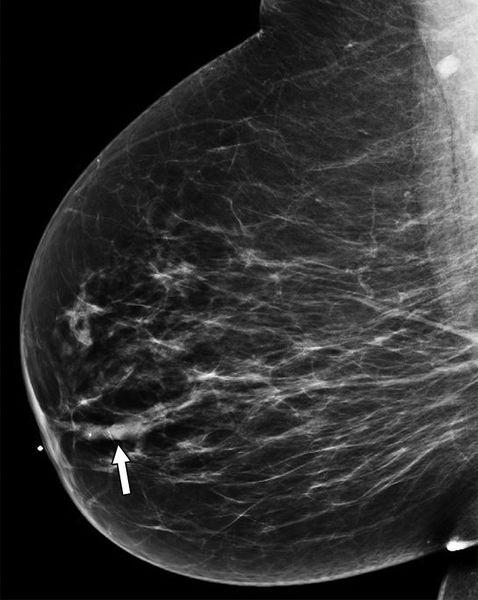

Расширенный молочный проток на маммограмме [6]

- Маммографию. Рекомендуется женщинам старше 40 лет, более молодым пациенткам её проводят только при подозрении на злокачественную опухоль. Позволяет оценить плотность тканей и обнаружить микрокальцинаты. Также помогает в дифференциальной диагностике с опухолевыми процессами.